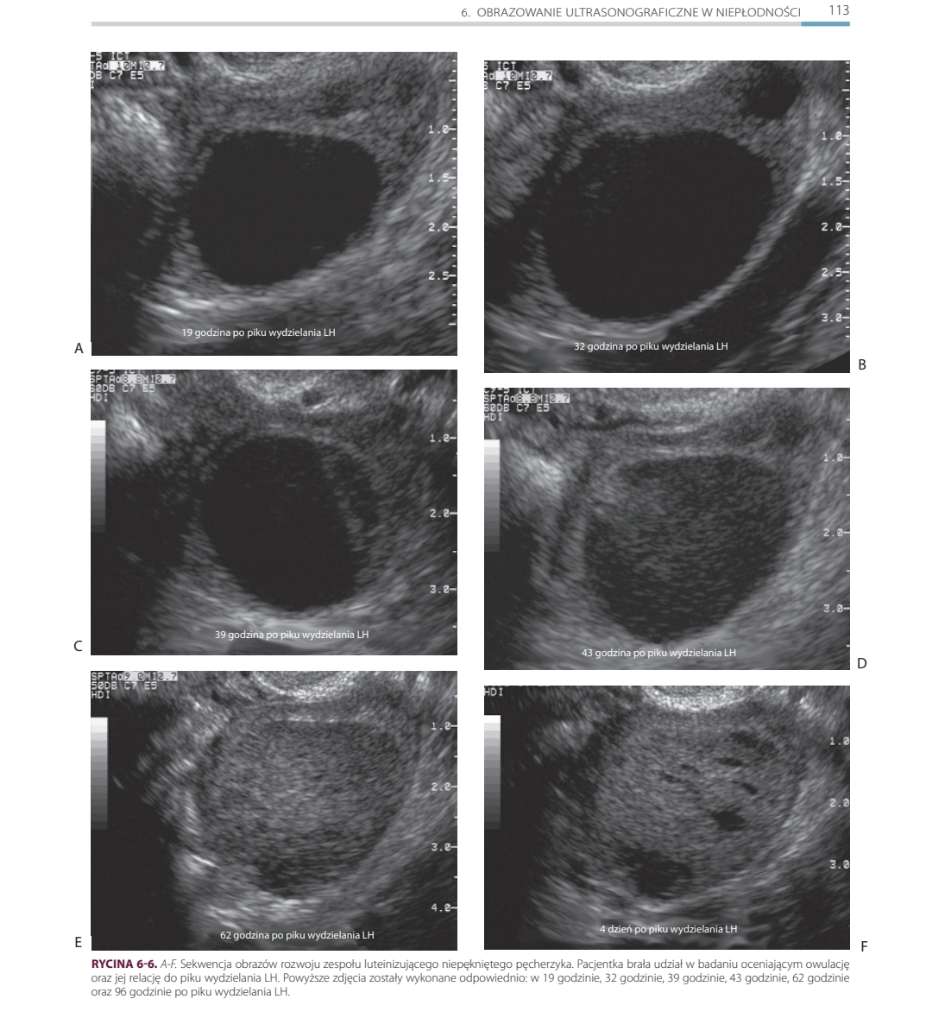

Dodaję zdj mojego USG z jednego z cykli kiedy miałam USG przed i po owulacji.

Jak dla mnie to te ciałko żółte wygląda jak jakiś zaburzony pęcherzyk bo ma jakieś kropki. 😅😂

Aktualna ginekolog stwierdziła, że nie do końca tak powinno wyglądać.

Wygląda jak nie ciałko żółte 😅 w sumie wygląda jak ten zluteinizowany pęcherzyk z artykułu, który czytałam...

Nie wiem czy będziecie widziały opisy pod zdjęciami a są dość istotne 🤔

I właśnie o tym mówię. Wg większości ginów to jest ciałko żółte i prog na to wskazuje- 6-7dni po "owulacji" był 19ng. A u mnie to zawsze- tzn jak mam monitoring po owu tak wygląda.

Dlatego mówię, że u mnie to podejrzewa gin ale nie może tego jednoznacznie stwierdzić. 😅

Tzn ta nowa dopiero zaczyna mnie leczyć i u niej już zostaję do końca mojej kariery staraczki więc dowiem się za kilka miesięcy czy to LUF czy taka moja natura.